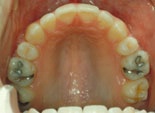

Trångställt bett

trångställt bett före behandling trångställt bett efter behandling

Före behandling av trångstätt bett Efter behandling av trångställt bett

Ett trångställt bett med för smal käke, i vy mot gommen. Således en kombination av en malocklusion och en utrymmesanomali. Om man behandlar liknande anomalier i rätt tid under ungdomsåren kan man till och med, som här, bredda käken med hjälp av tandreglering. Barnets egen växt hjälper till.